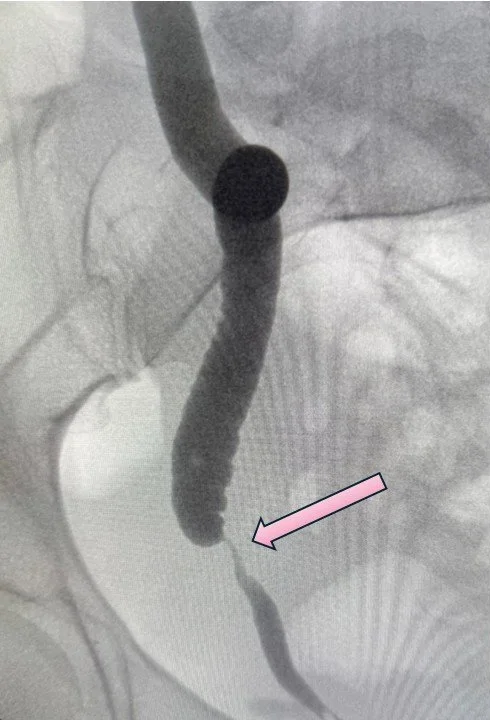

The image on the left is an x-ray of a patient sent to me with an injured ureter. The ureter is the long thin tube, but the bottom section of the doesn’t make it all the way down to the bladder, the round structure on the bottom left. There is a bad scar that formed - a stricture - that completely obliterated the ureter tube hollow center, so no urine could drain. This is called a "distal" stricture because it is the bottom of the ureter, closest to the bladder and furthest from the kidney. I performed a robotic ureteral reimplant with a Boari flap (image on the right) and fixed the problem. A Boari flap is a procedure where you use part of the bladder wall to make a new connection up to the ureter.